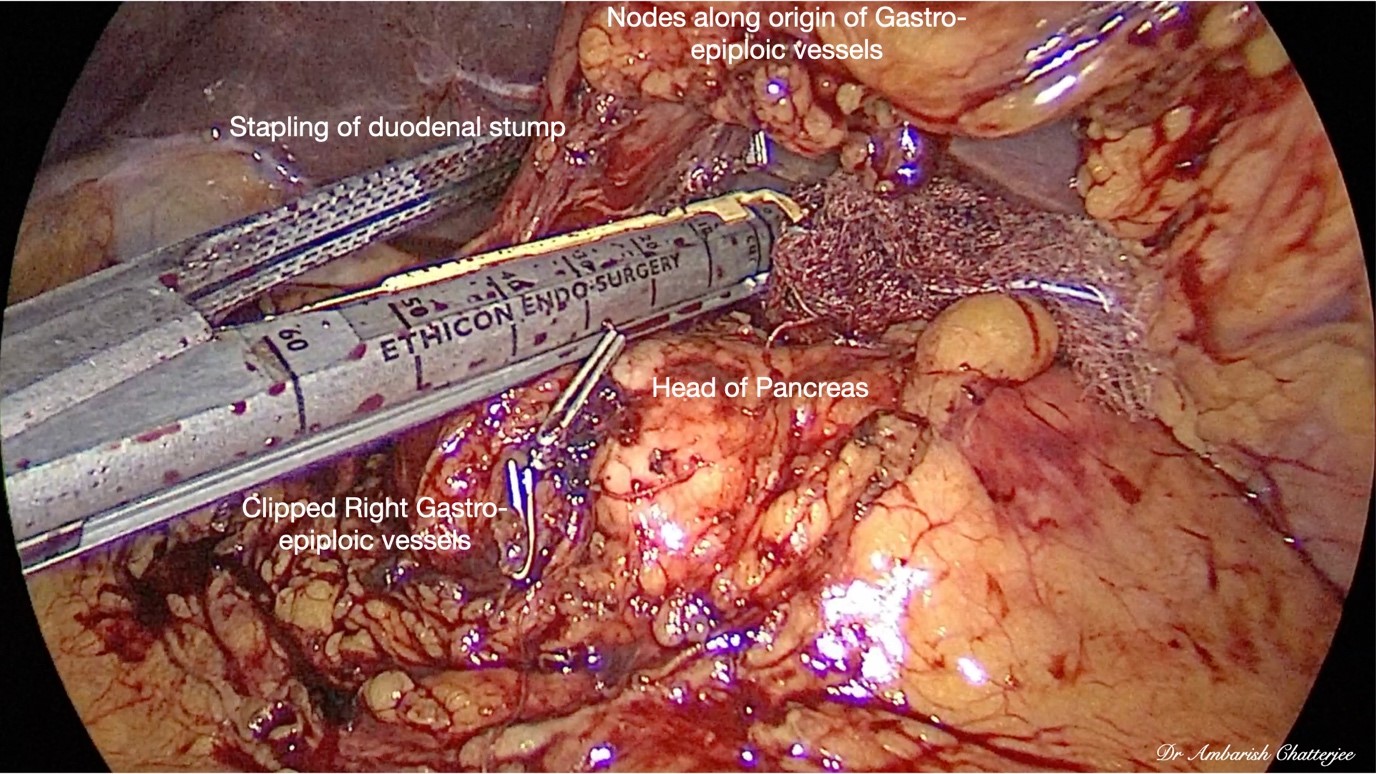

50 years old gentleman, diagnosed with gastric adenocarcinoma with gastric outlet obstruction. On CT scan the disease was localized to distal part of stomach. The patient underwent upfront laparoscopic subtotal gastrectomy with D2 lymphadenectomy and extracorporeal gastro-jejunal anastomosis. The intra-operative and post-operative period was uneventful. The patient was discharged on 7th post-operative day.